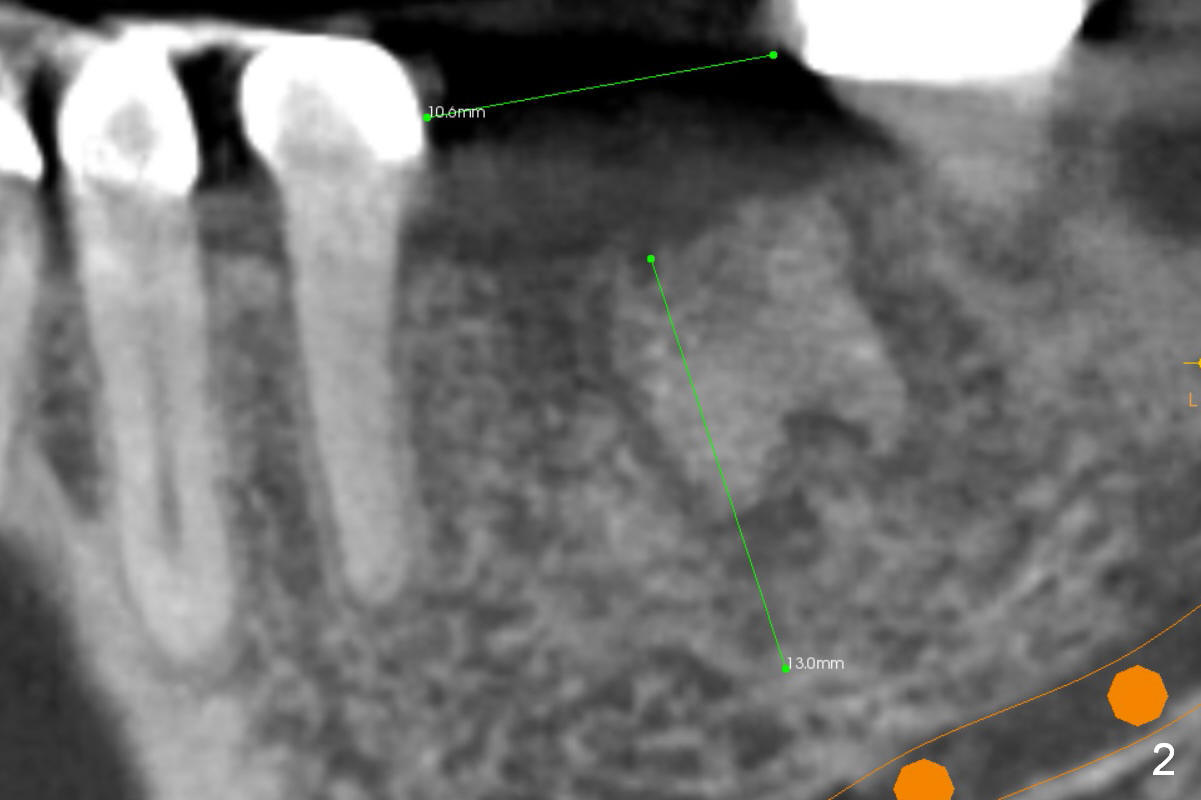

Mesial Socket of 1st Molar

The mesiodistal dimension of the edentulous area is 10.6 mm, one molar width (Fig.2). Therefore, one implant is appropriate for the site and will be placed in the mesial socket of the 1st molar. Although bone density of xenograft is high (1000 units (200 units soft bone)), try bone expansion for an implant as large as possible (Fig.3). It seems that a 11 mm long IBS implant is safer than the 13 mm one, since the latter is closer to the submandibular fossa (F). A 4.5x11 mm one may be the most proper.